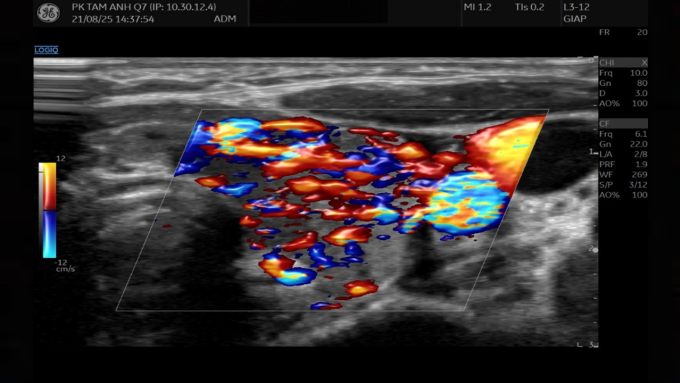

Kết quả siêu âm cho thấy nhu mô tuyến giáp không đồng nhất, tăng tưới máu. Ảnh: Phòng khám Đa khoa Tâm Anh Quận 7